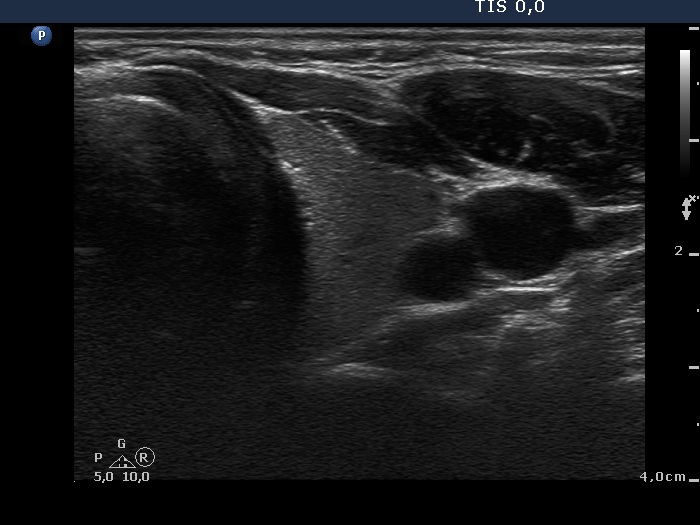

Third examination 24 months after initial investigation (3rd row of images)

Clinical data: The thyrostatic therapy was stopped 13 months ago. The patient had no complaints.

Palpation: unchanged.

Results of blood tests: euthyroidism (TSH 0.52 mIU/L, FT4 14.6 pM/L).

Ultrasonography: The size of the thyroid decreased further. The echo structure and the vascularization became normal.

Suggestion: to check the thyroid function every year, in the event of complaints or pregnancy at once.

Comment. This case demonstrates typical course of non-relapsing Graves disease. The change in hormone levels and in the ultrasound pattern are parallel.